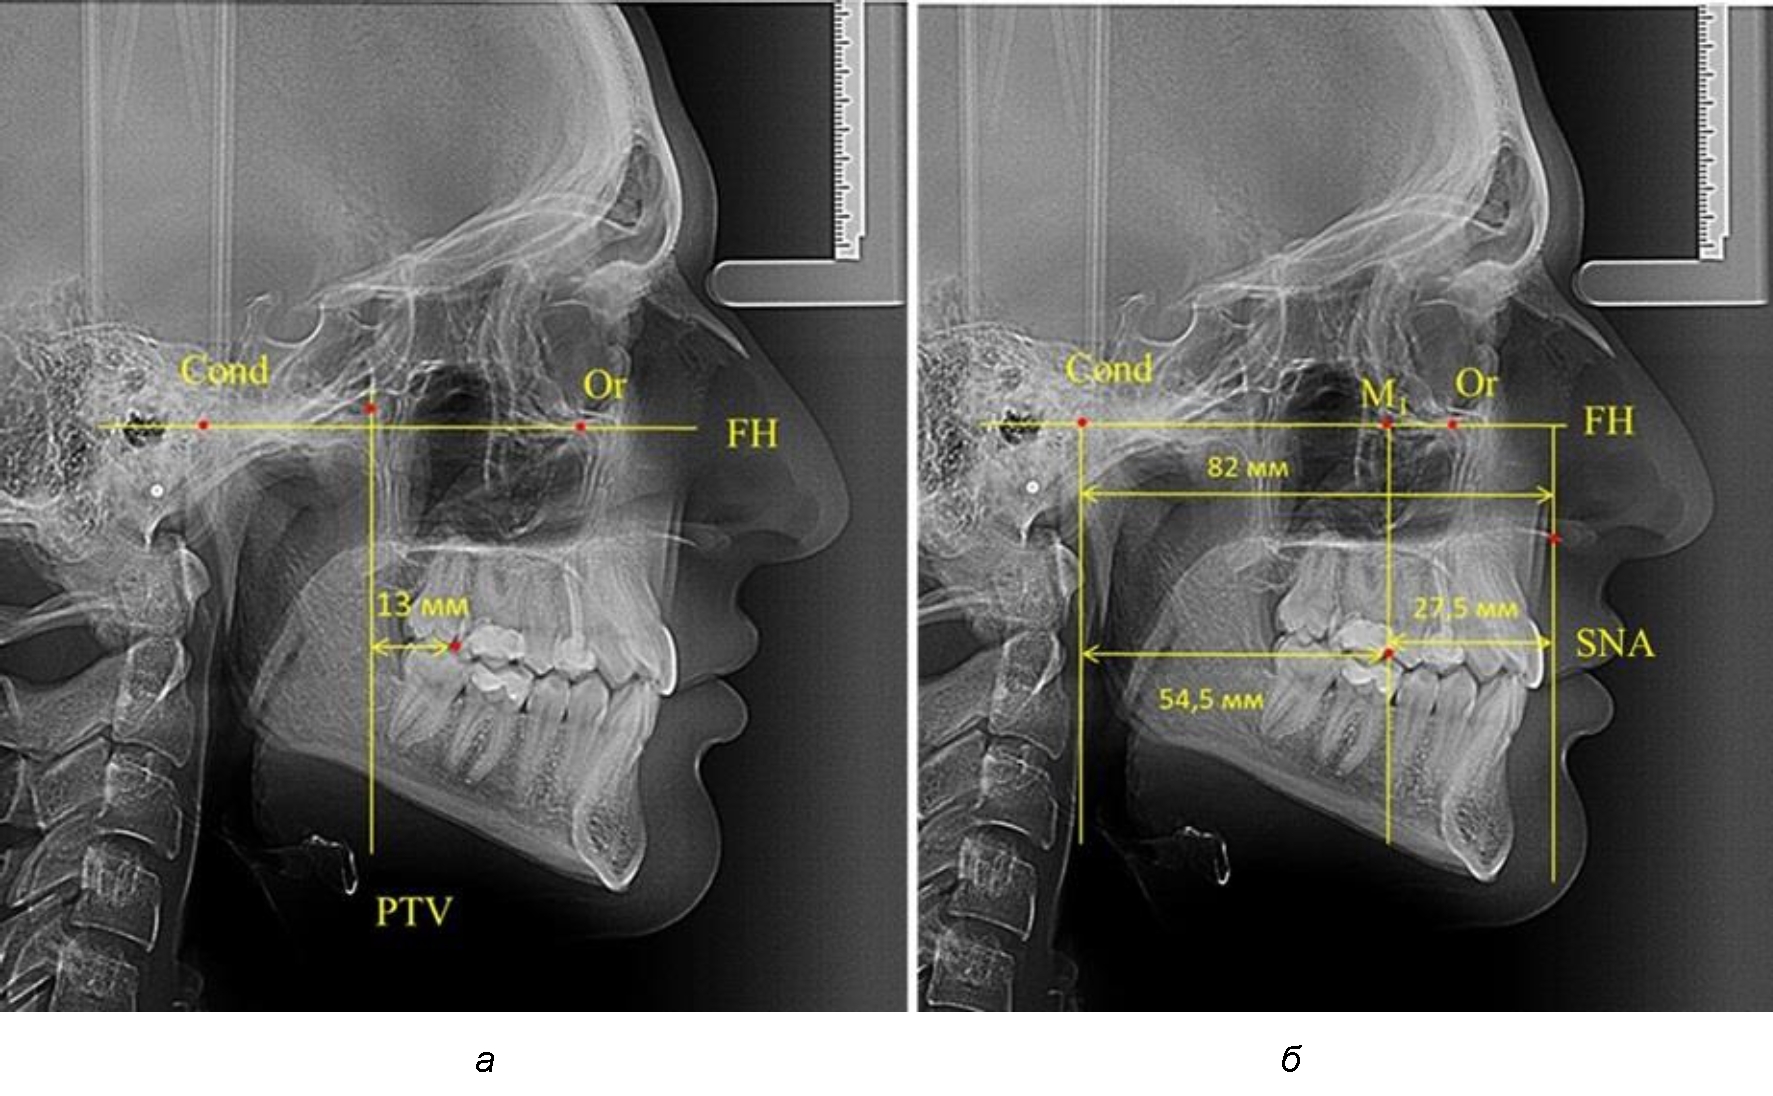

Рис. 1. Метод определения положения первых верхних моляров по Ralph E. McDonald (а) и по предложенному методу (б)

Согласно указанному методу на рентгенограммах проводили Франкфуртскую горизонталь. Учитывая мнения специалистов относительно ориентиров для построения и вариабельность положения наружного слухового прохода, в качестве задней точки использовали верхнюю выпуклость суставной головки нижней челюсти («Cond»). Передняя точка традиционно располагалась на нижнем крае глазницы и определялась как орбитальная точка Or.

Находили положение точки Pt, которая располагалась на пересечении нижнего края круглого отверстия и задней стенки крыловидно-верхнечелюстной щели, и перпендикулярно к Франкфуртской горизонтали проводили крыловидную вертикальную линию, которую принято обозначать как плоскость PTV. Расстояние от крыловидной вертикальной плоскости PTV до дистальной поверхности верхнего первого постоянного моляра определяло его положение, которое, по мнению R. E. McDonald, соответствовало возрасту пациента, увеличенному на 3 мм.

При проведении анализа к Франкфуртской горизонтали проводили передний и задний перпендикуляры. Передний спинальный перпендикуляр проходил через выступающую точку передней носовой ости (spina nasalis anterior – SNA), а задний суставной перпендикуляр опускали из кондилярной точки Cond. Молярный перпендикуляр проводили через медиальную поверхность первого постоянного моляра. Указанная вертикаль отделяла замещающие зубы постоянного прикуса от добавочных зубов (постоянных моляров), что вполне логично для анализа положения первых постоянных моляров в гнатическом комплексе (рис. 1).

Если метод R. E. McDonald позволял оценить только положение первых постоянных верхних моляров, то предложенный метод учитывал сагиттальные индивидуальные размеры гнатического отдела лица и определять соотношение межу его размерами в передней и задней части.